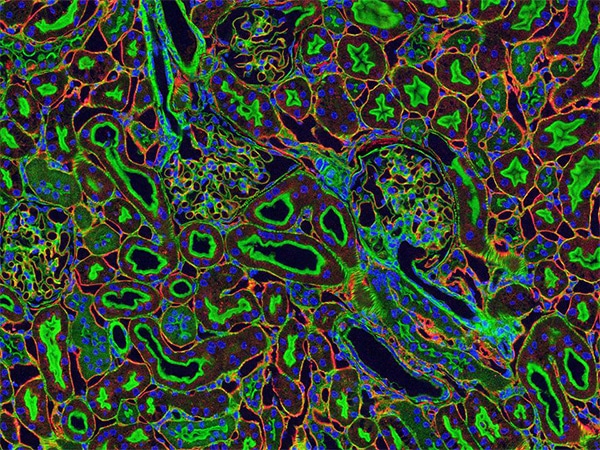

Credit: Tom Deerinck and Mark Ellisman, National Center for Microscopy and Imaging Research